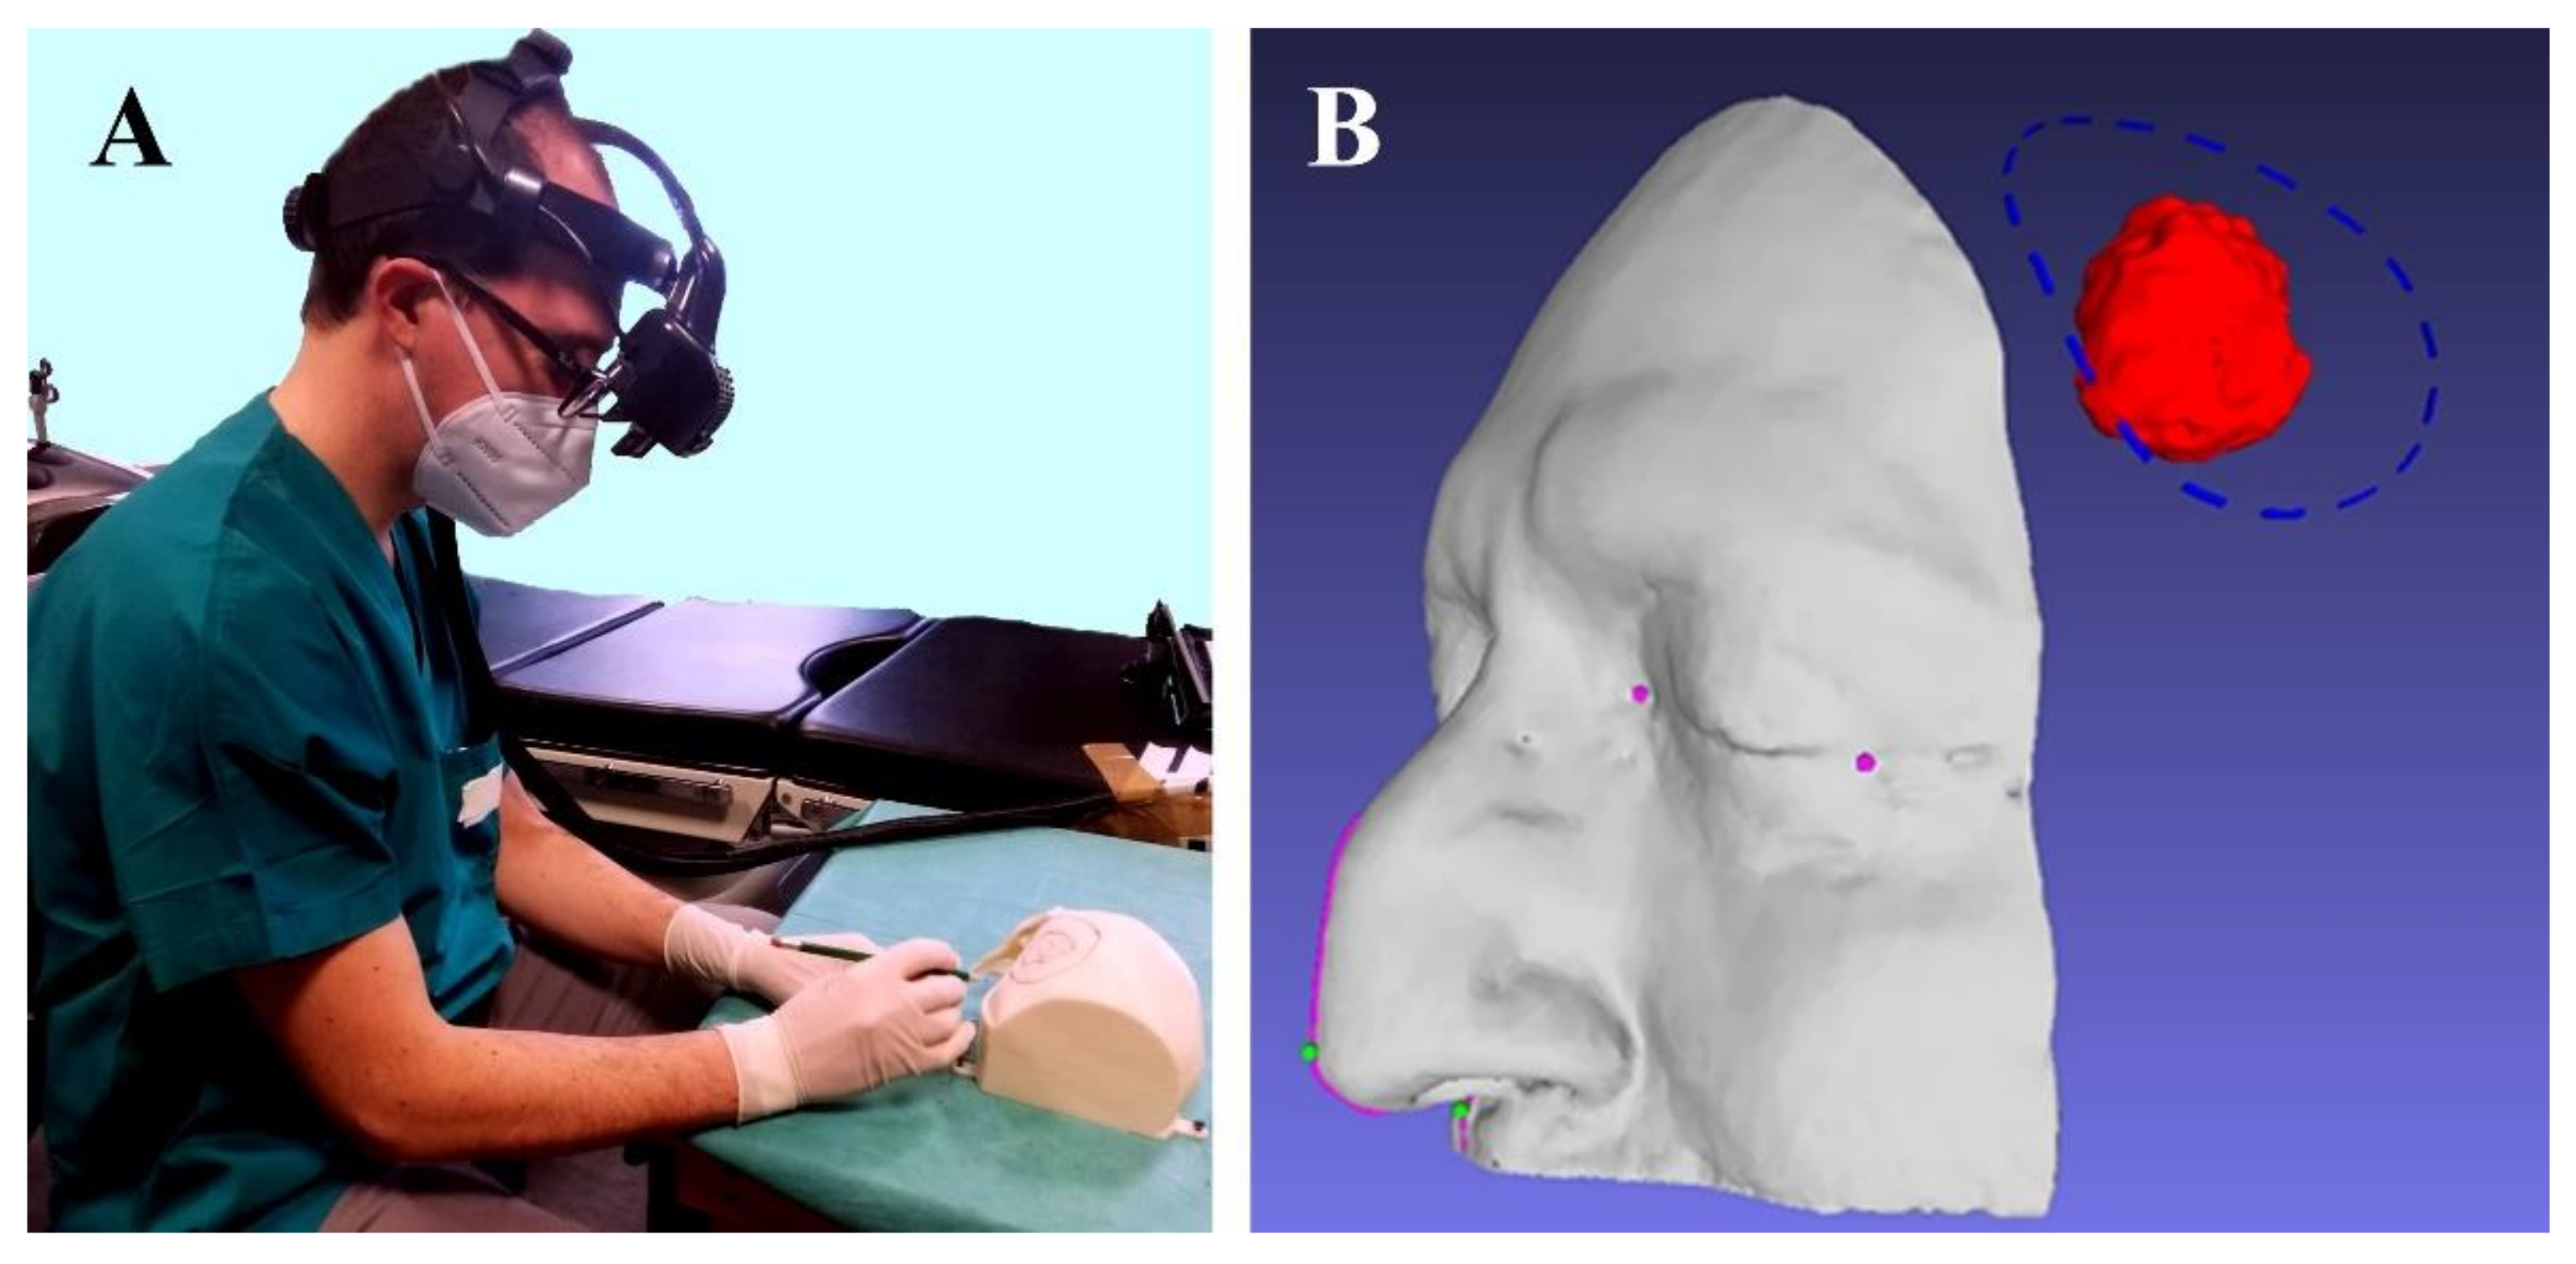

2.1. Case Description